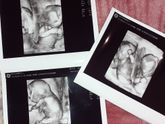

Всем привет?♀️. Вот и пошла наша 15-ая неделька. Живот уже прилично видно?, его уже не спрячешь) я чувствую своих карапузов, не отчетливых движений или толчков пока что нет? завтра мне на УЗИ снова. Токсикоз пока что меня не покинул, но самочувствие … Читать далее